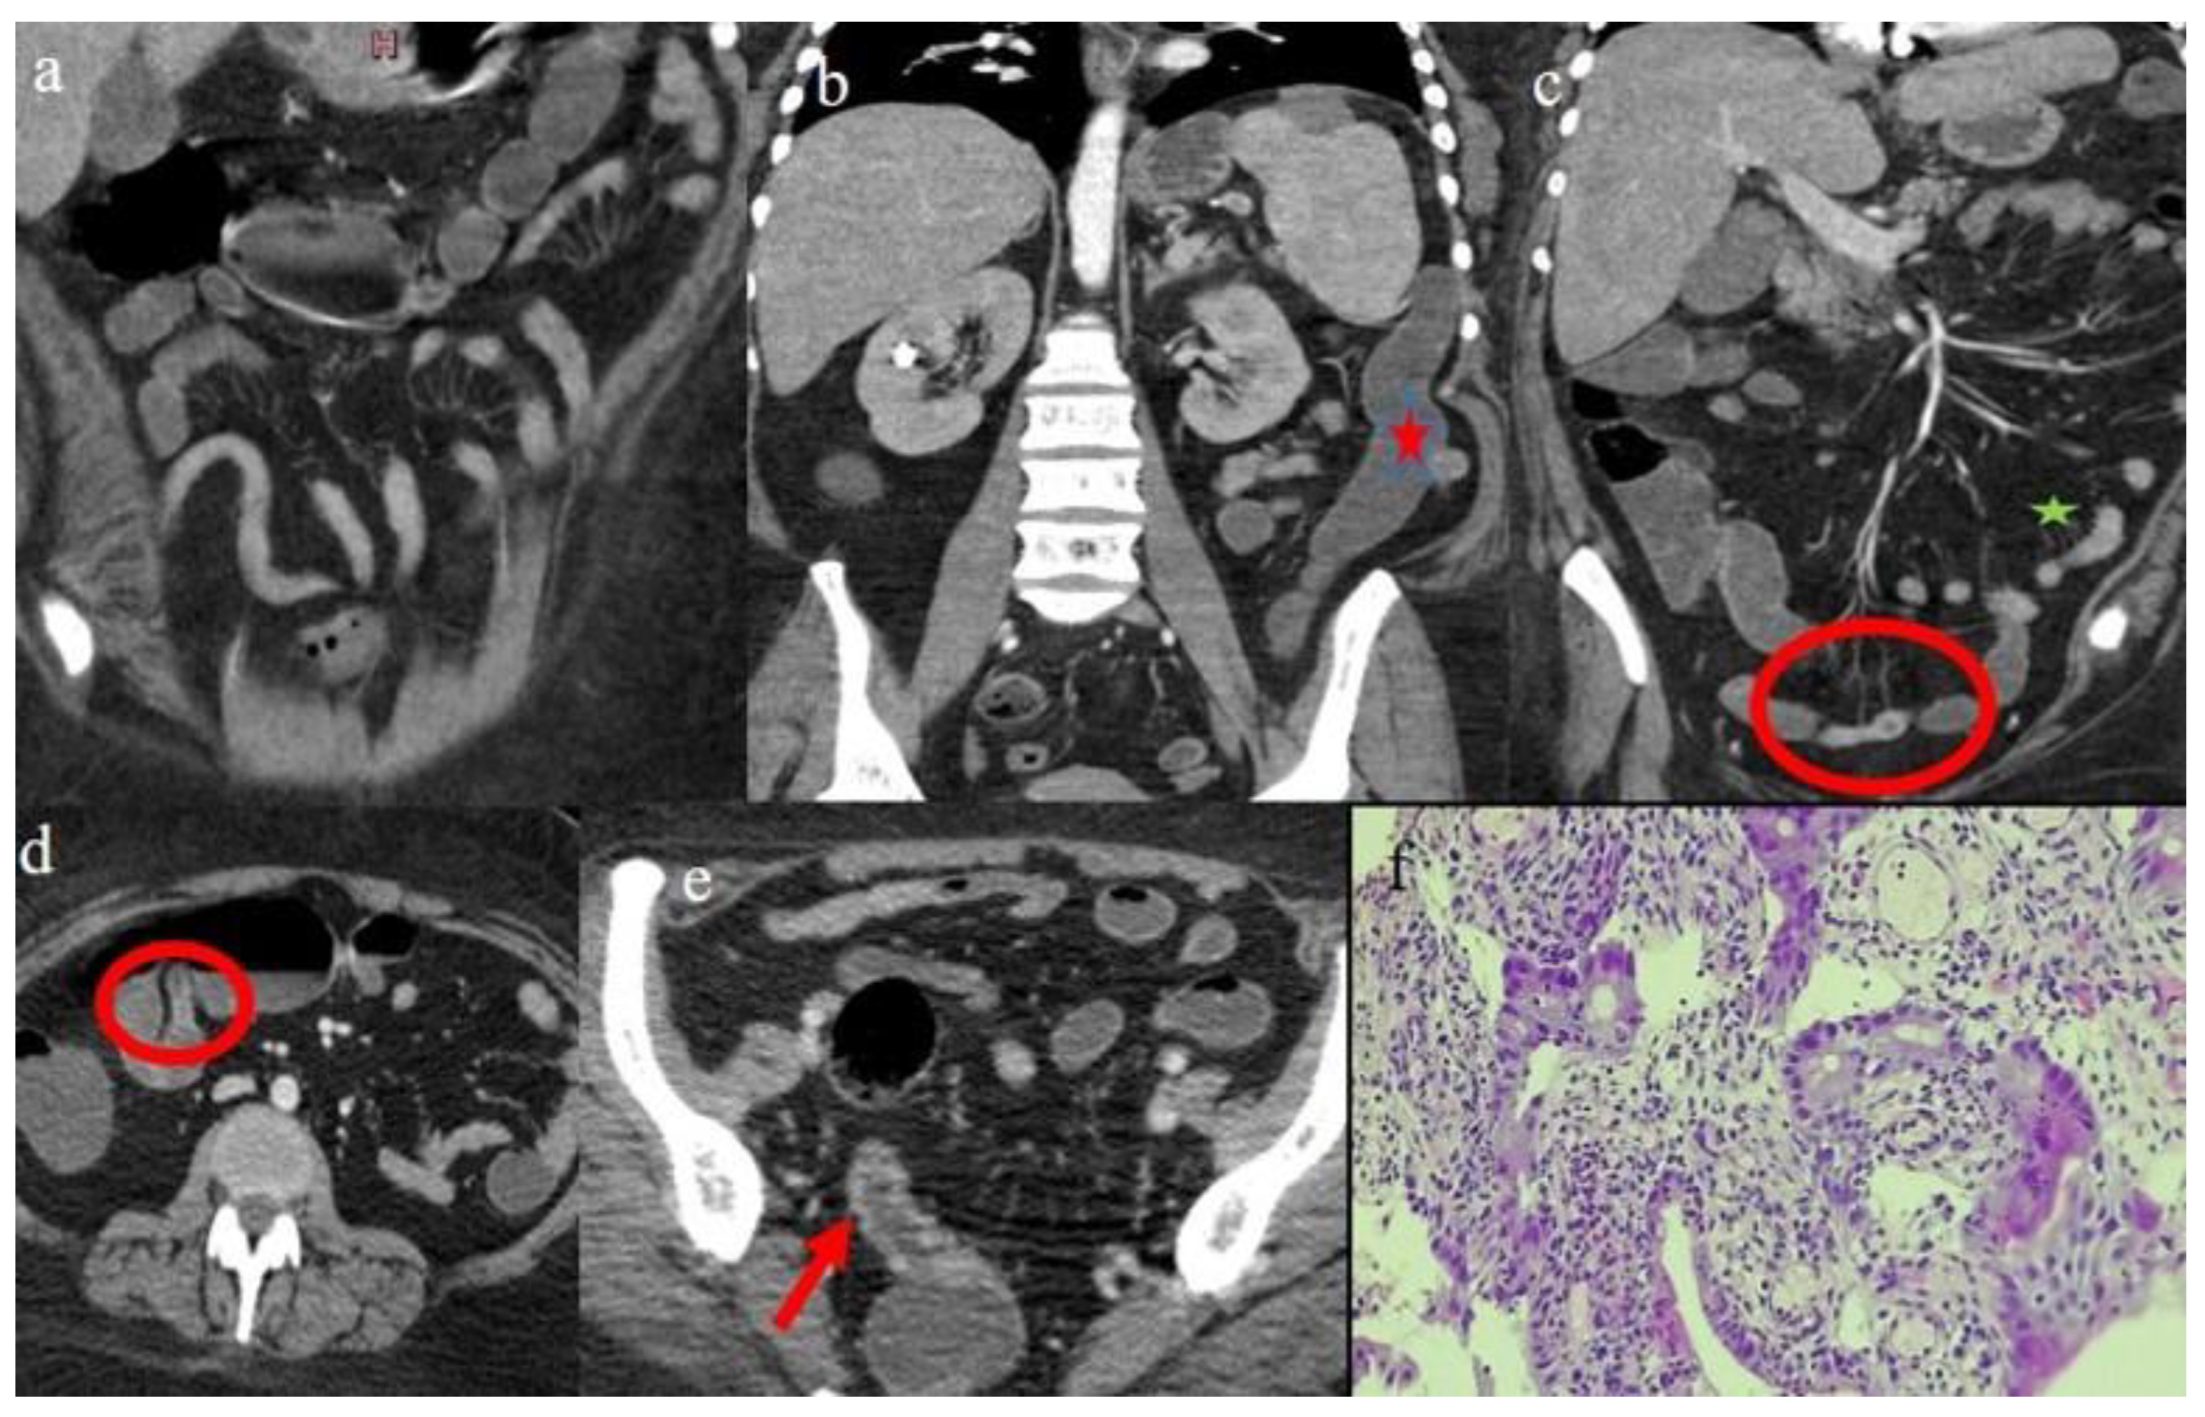

| 5 | P | P | Multisegmental thickness with stenosis on jejunal loops and SBO and segmental and focal thickness on the terminal ileus and appendix | Diffuse parietal thickness with stratified enhancement | Mild comb sign, poor reactive mesenteric lymph node, small air bubbles in the ascites | Small splenic areas of ischemia |